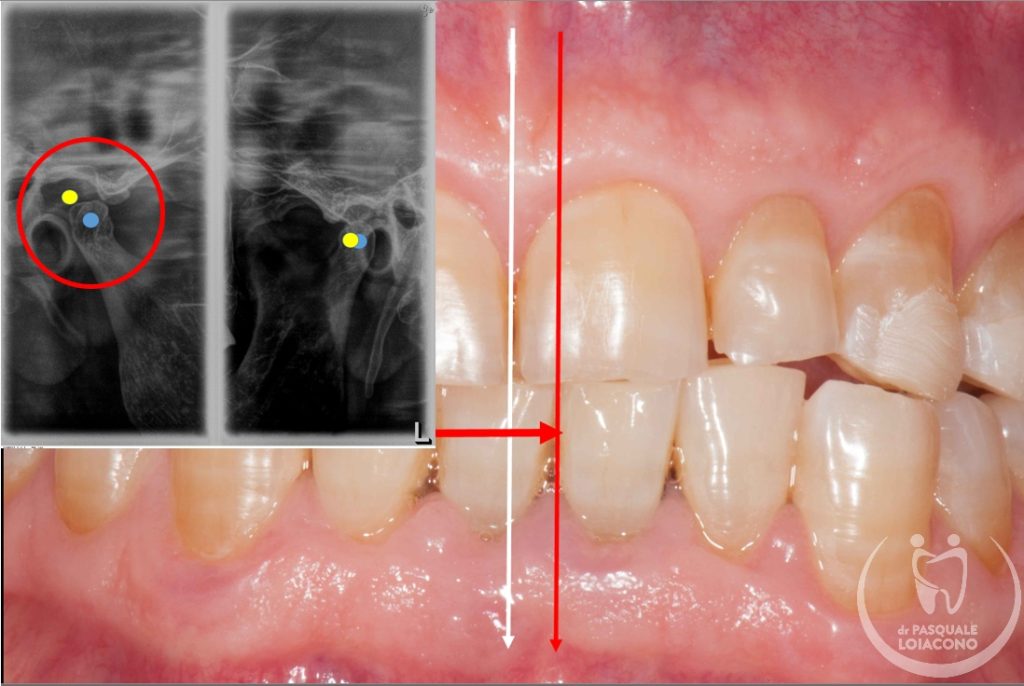

E’ importante notare come sia la chiusura dentale a influenzare la posizione nello spazio dell’articolazione. Per questo in caso di problemi articolari è necessario costruire un bite di “riposizionamento mandibolare”, cioè un apparecchio costruito per mantenere attraverso i denti la mandibola e le sue articolazioni in una posizione corretta.

Quando ci sono problemi articolari della mandibola è necessario ricercare un’occlusione dentaria che rimetta il sistema il più possibile in equilibrio. L’organo della masticazione non è costituito solo da denti, ma anche da articolazioni e componenti neuromuscolari, e solo quando tuti i componenti sono in armonia tra loro si può avere salute e benessere. In realtà non tutti gli studiosi sono d’accordo su questioni fondamentali e non esiste visione unanime. Questo vuol dire che potreste incontrare un odontoiatra che sconsiglia qualsiasi trattamento, se non fisioterapia e massaggi o addirittura solo terapia psicologica di sostegno. All’opposto esistono scuole di pensiero che identificano nell’occlusione il fattore scatenante di una patologia che comunque resta complessa e multifattoriale. Da dentista desidero che la bocca funzioni bene e segua le regole stabilite, perché considero comunque positiva questa condizione, e quindi cerco di riportare l’occlusione del paziente verso una condizione il più possibile ideale.